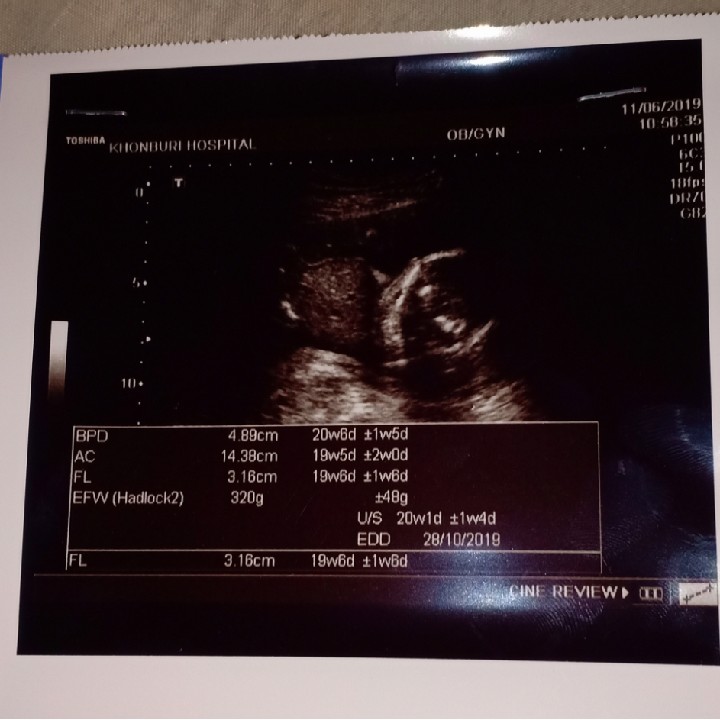

20wค่ะ

20wค่ะ